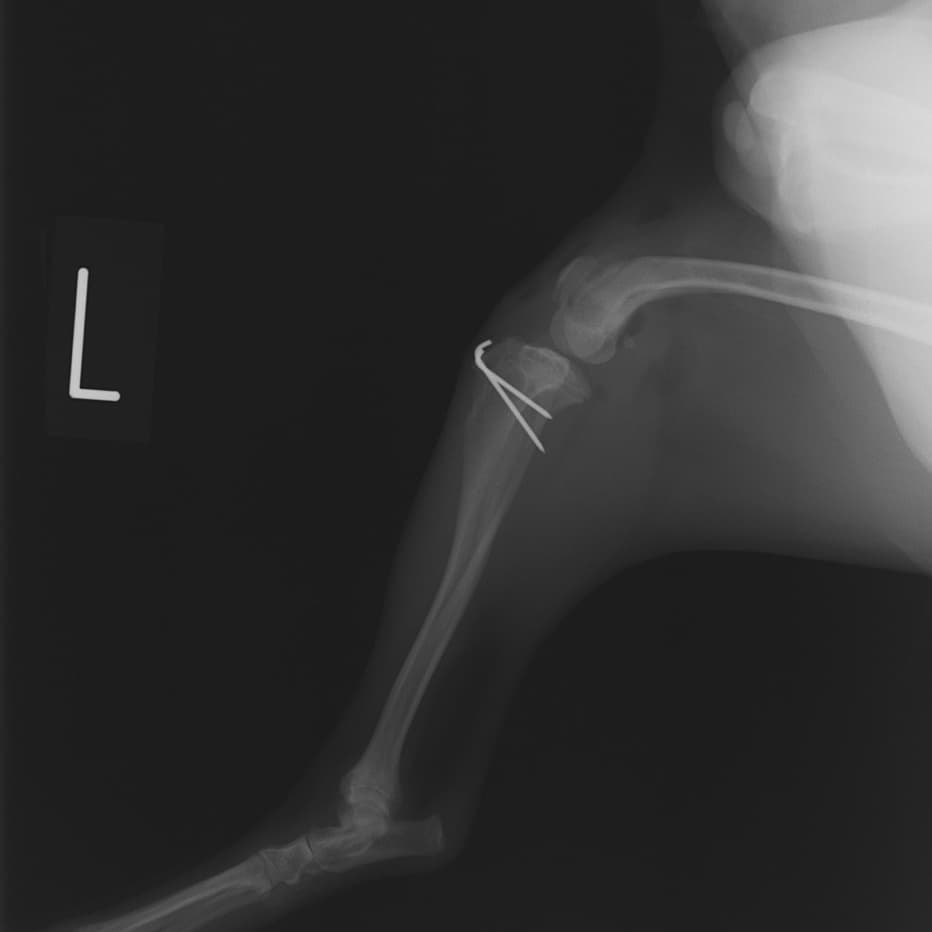

■ 症例24 キャバリア 7か月

左右膝蓋骨内方脱臼(左:グレードⅣ 右:グレードⅢ)

以前から左右後肢の跛行が認められ、整形外科学的検査・レントゲン検査により左右の膝蓋骨脱臼が認められた。症状が重度である左膝の膝蓋骨脱臼整復術を行った。外科手技は縫工筋及び内側広筋の解放、脛骨粗面の外側転位、滑車ブロック形造溝術、内外側関節方の縫縮を実施した。術後一か月時点で、左の膝蓋骨は安定しており経過は良好である。

本症例は成長期における重度の膝蓋骨脱臼であり、術後の再発の可能性もあるため、経過をしっかりと観察していく必要がある。また、今回手術を実施していない右膝に関しても経過を観察し、手術を検討していくこととする。